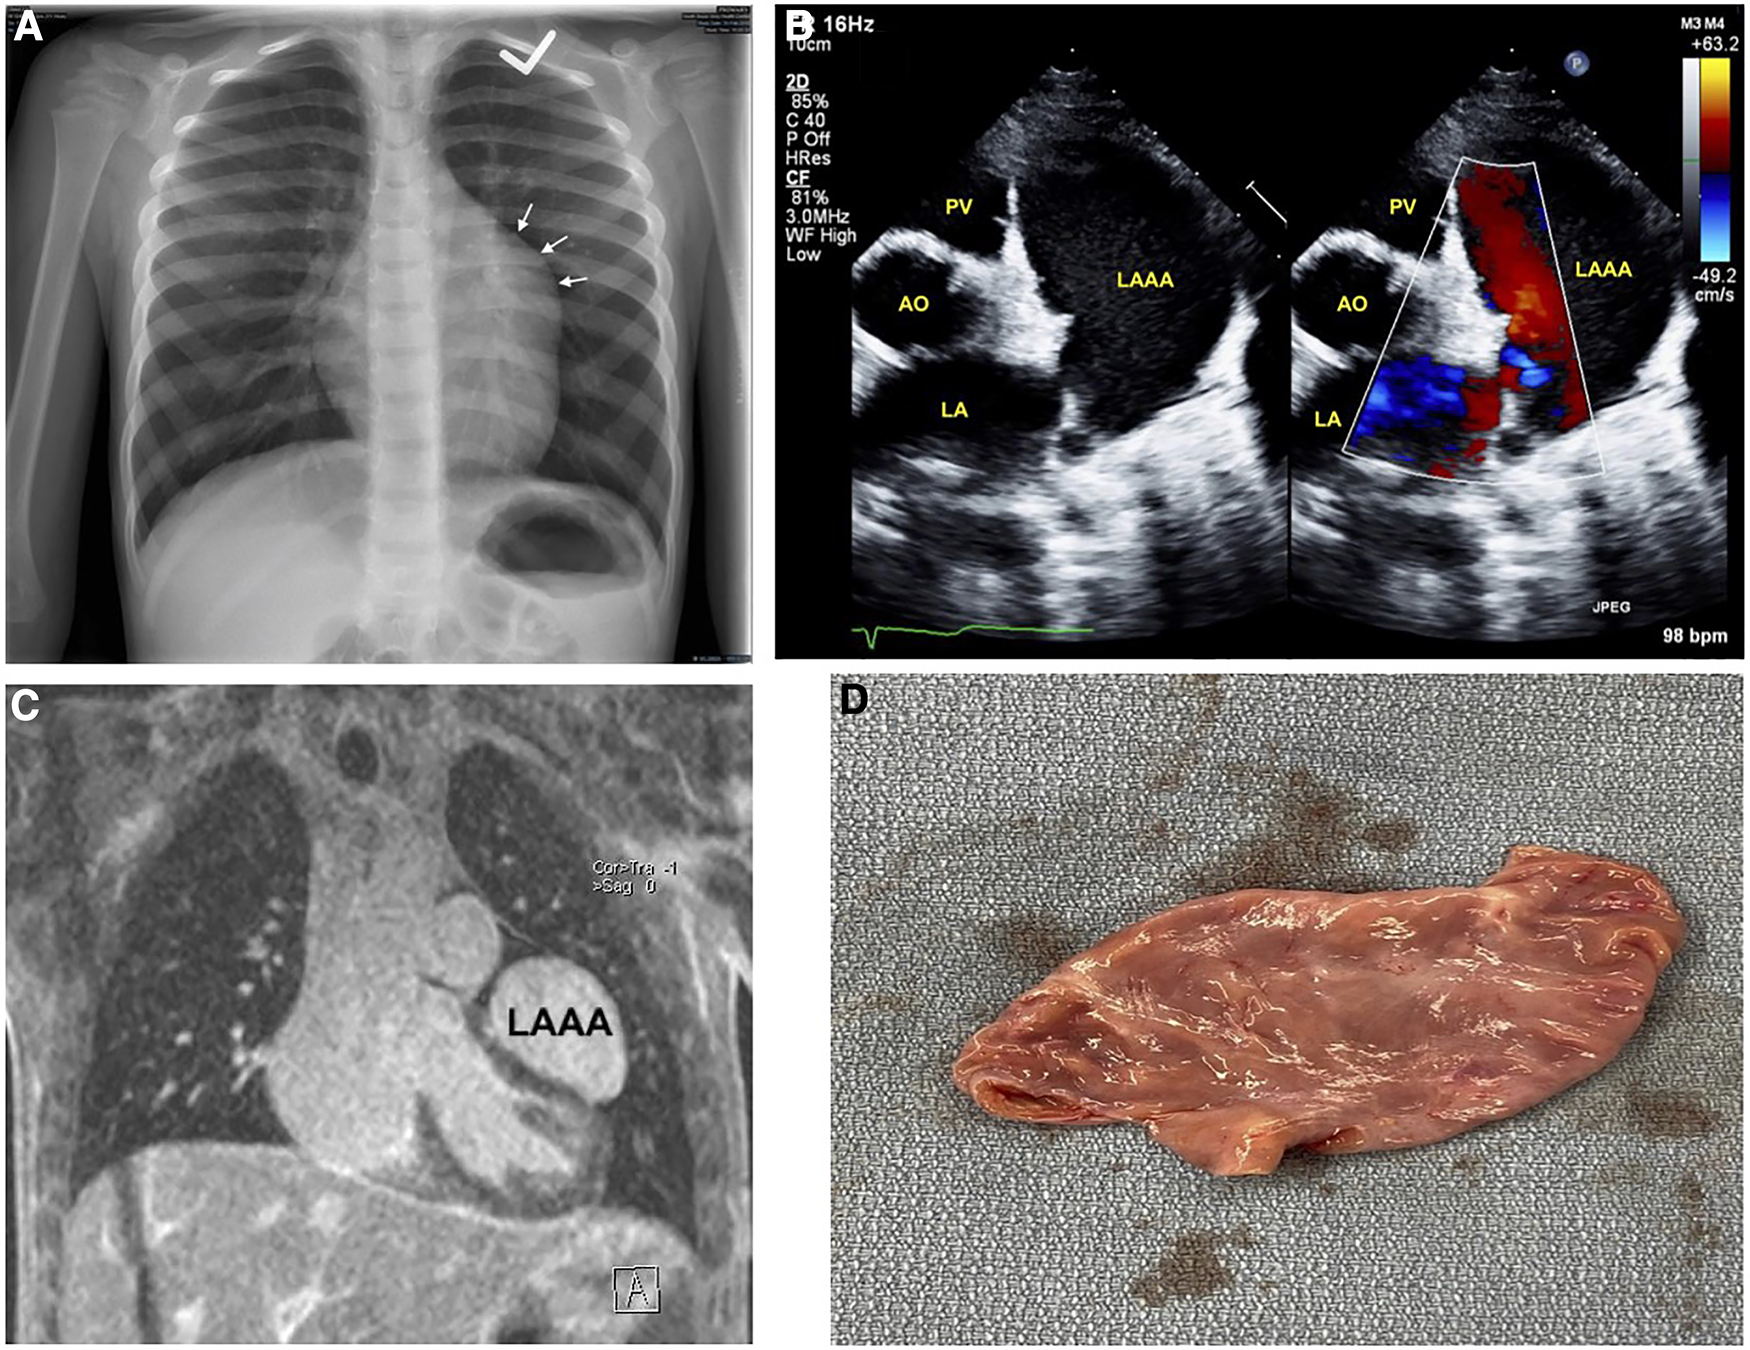

An otherwise healthy 6-year-old boy was referred to pediatric cardiology due to an incidentally discovered abnormal cardiac silhouette on a chest x-ray performed during an investigation of scarlet fever with cough (Figure 1A). On history, he was active, able to keep up with his peers, and had no history of cyanosis, syncope, chest pain, or palpitations. There was no family history of congenital cardiac anomalies or early unexplained deaths. His physical exam revealed a well-appearing boy in no distress; height 128 cm and weight 23.9 kg. A cardiac exam revealed a quiet precordium with no heaves or thrills, regular S1 and normally split S2 with no extra heart sounds or murmurs. Right arm (102/64) and left arm (115/66) blood pressures were normal. There was no hepatomegaly, and the respiratory exam was normal: respiratory rate of 24 and oxygen saturation of 98%.

Imaging of left atrial appendage aneurysm. (A) Initial chest x-ray showing an unusual contour along the left heart border. (B) Transthoracic echocardiography short-axis sweep with colour doppler demonstrating a cavity adjacent to and potentially communicating with the left atrium. (C) Magnetic resonance imaging revealing the LAAA, and compressing the left ventricular anterior and anteroseptal walls. (D) Post-operative image of the resected LAAA measuring 5.9 × 3.1 × 1.9 cm. AO, aorta; LA, left atrium; LAAA, left atrial appendage aneurysm; PV, pulmonary valve.

An electrocardiogram was performed and showed normal sinus rhythm. Subsequent baseline echocardiography showed a giant LAAA with otherwise regular heart structure, size, and function (Figure 1B) (Supplementary Data Sheet S1). This was later confirmed with magnetic resonance imaging, which also showed mild compression of the left ventricular anterior and anteroseptal walls (Figure 1C). Surgical intervention was favoured for prophylaxis against compressive or thrombotic events. He underwent surgical resection without any intraoperative complications.

Post-operatively, he initially had vasoplegia that resolved with a transfusion of one unit of packed cells and norepinephrine. Pathology revealed an appendage measuring 5.9 × 3.1 × 1.9 cm, without blood clots (Figure 1D). His 3-day postoperative course was uneventful. Echocardiography at his first post-operative clinic visit showed the LAAA had been plicated with otherwise normal cardiac structure and function. He remained asymptomatic with a normal physical exam, electrocardiogram, and echocardiography at his two-month, 12-month, and 24-month postoperative follow-ups (Table 1).